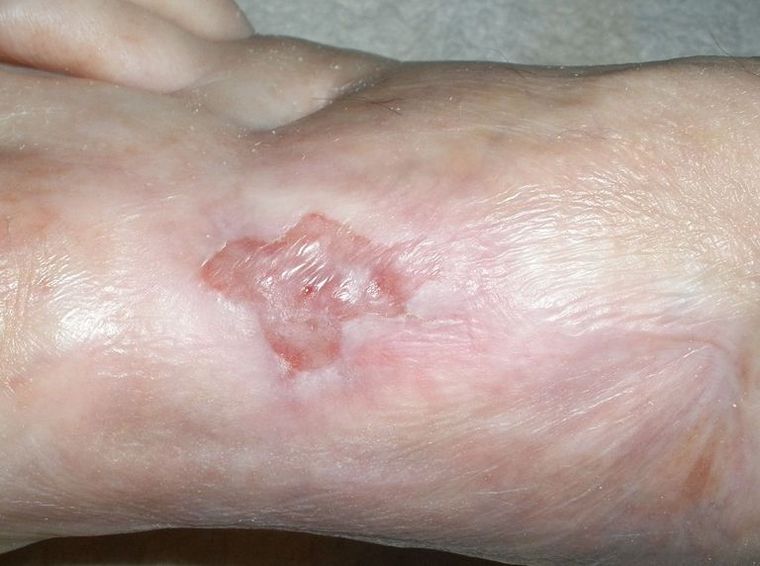

Das ist der Grund wieso momentan nichts weitergeht, Foto Mitte 2008: